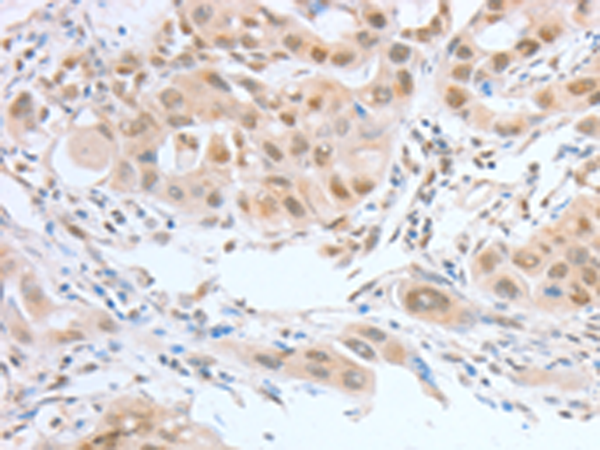

分类: 科研抗体货号: P07124别名: CREB2; TXREB; CREB-2; TAXREB67应用: IHC反应种属: Human, Mouse, Rat